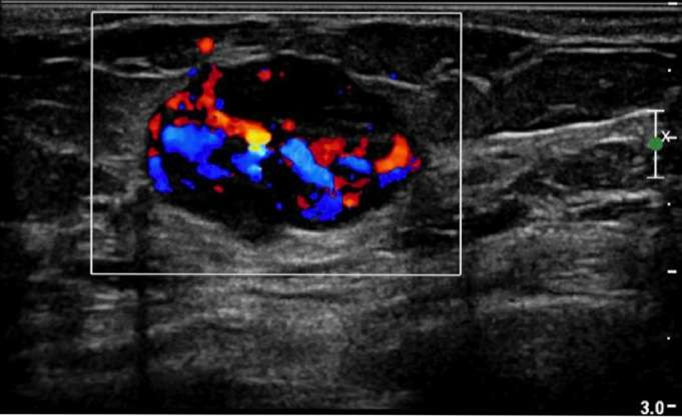

ultrasound in the breast used for whaT?

used to assess the vessels of the breasts

- deifferentiate between solid and cyst

what is used for used to assess the vessels of the breasts

- deifferentiate between solid and cyst?

US